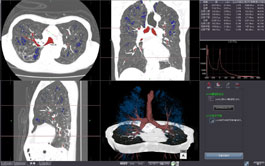

CT PA/PV AUTO-SEGMENTATION

This standard feature allows you to display lungs, bronchi, pulmonary artery and pulmonary veins simultaneously. Click on an individual structure to toggle its inclusion in the arterial or venous mask. Fusion of structures such as lesions or tumors is straightforward.

CT LUNG RESECTION PLANNING

High precision automatic segmentation of lungs, lung lobes, bronchi, pulmonary arteries and veins enable lung resection proposals based on bronchial or arterial anatomy.